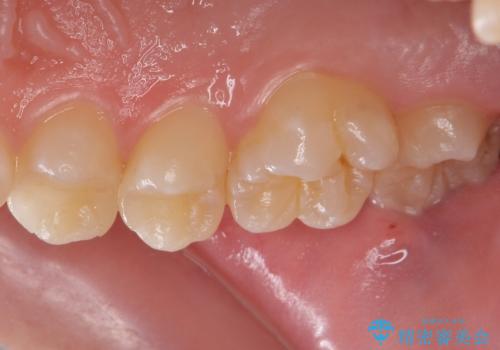

虫歯を取り除いた後、セラミックインレーで修復していきます。

- 右上45 セラミックインレー 77,000円×2本費用は治療当時の料金となります

適合の良い修復物を装着することで今後の虫歯リスクを抑えることができます。